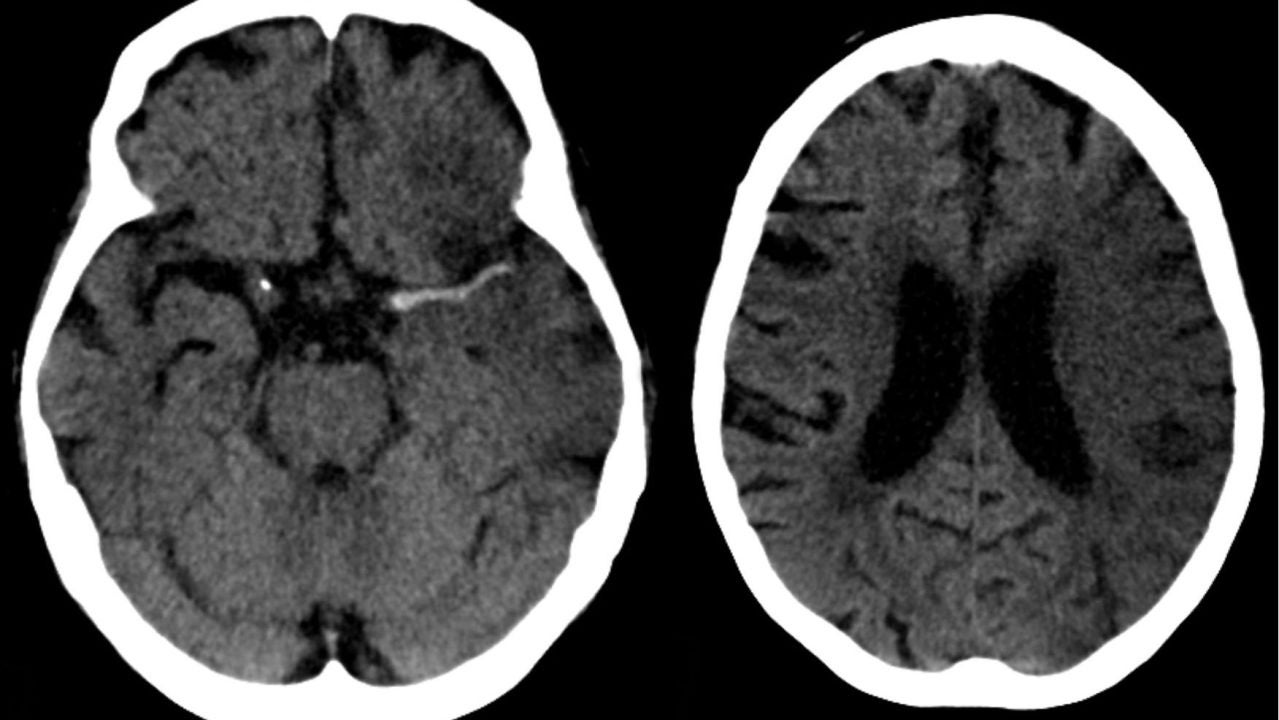

Ictus en arteria cerebral media (izda) y evolución a las 7 horas (dcha). wikipedia